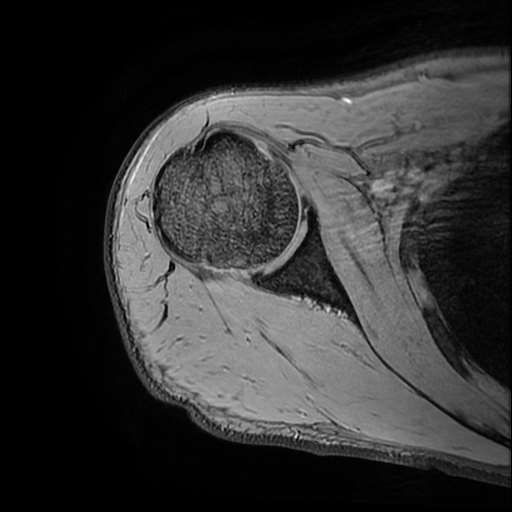

오른쪽 어깨 와순파열 및 점액낭염이 보인다고 하는데 상태를 알고 싶습니다

MRI 사진상 와순파열 점액낭염 등이 있다고 하는데..심한 상태인가요?

MRI상 와순파열, 회전근개 부분파열 등이 있으며 일부 염증소견이 있습니다.